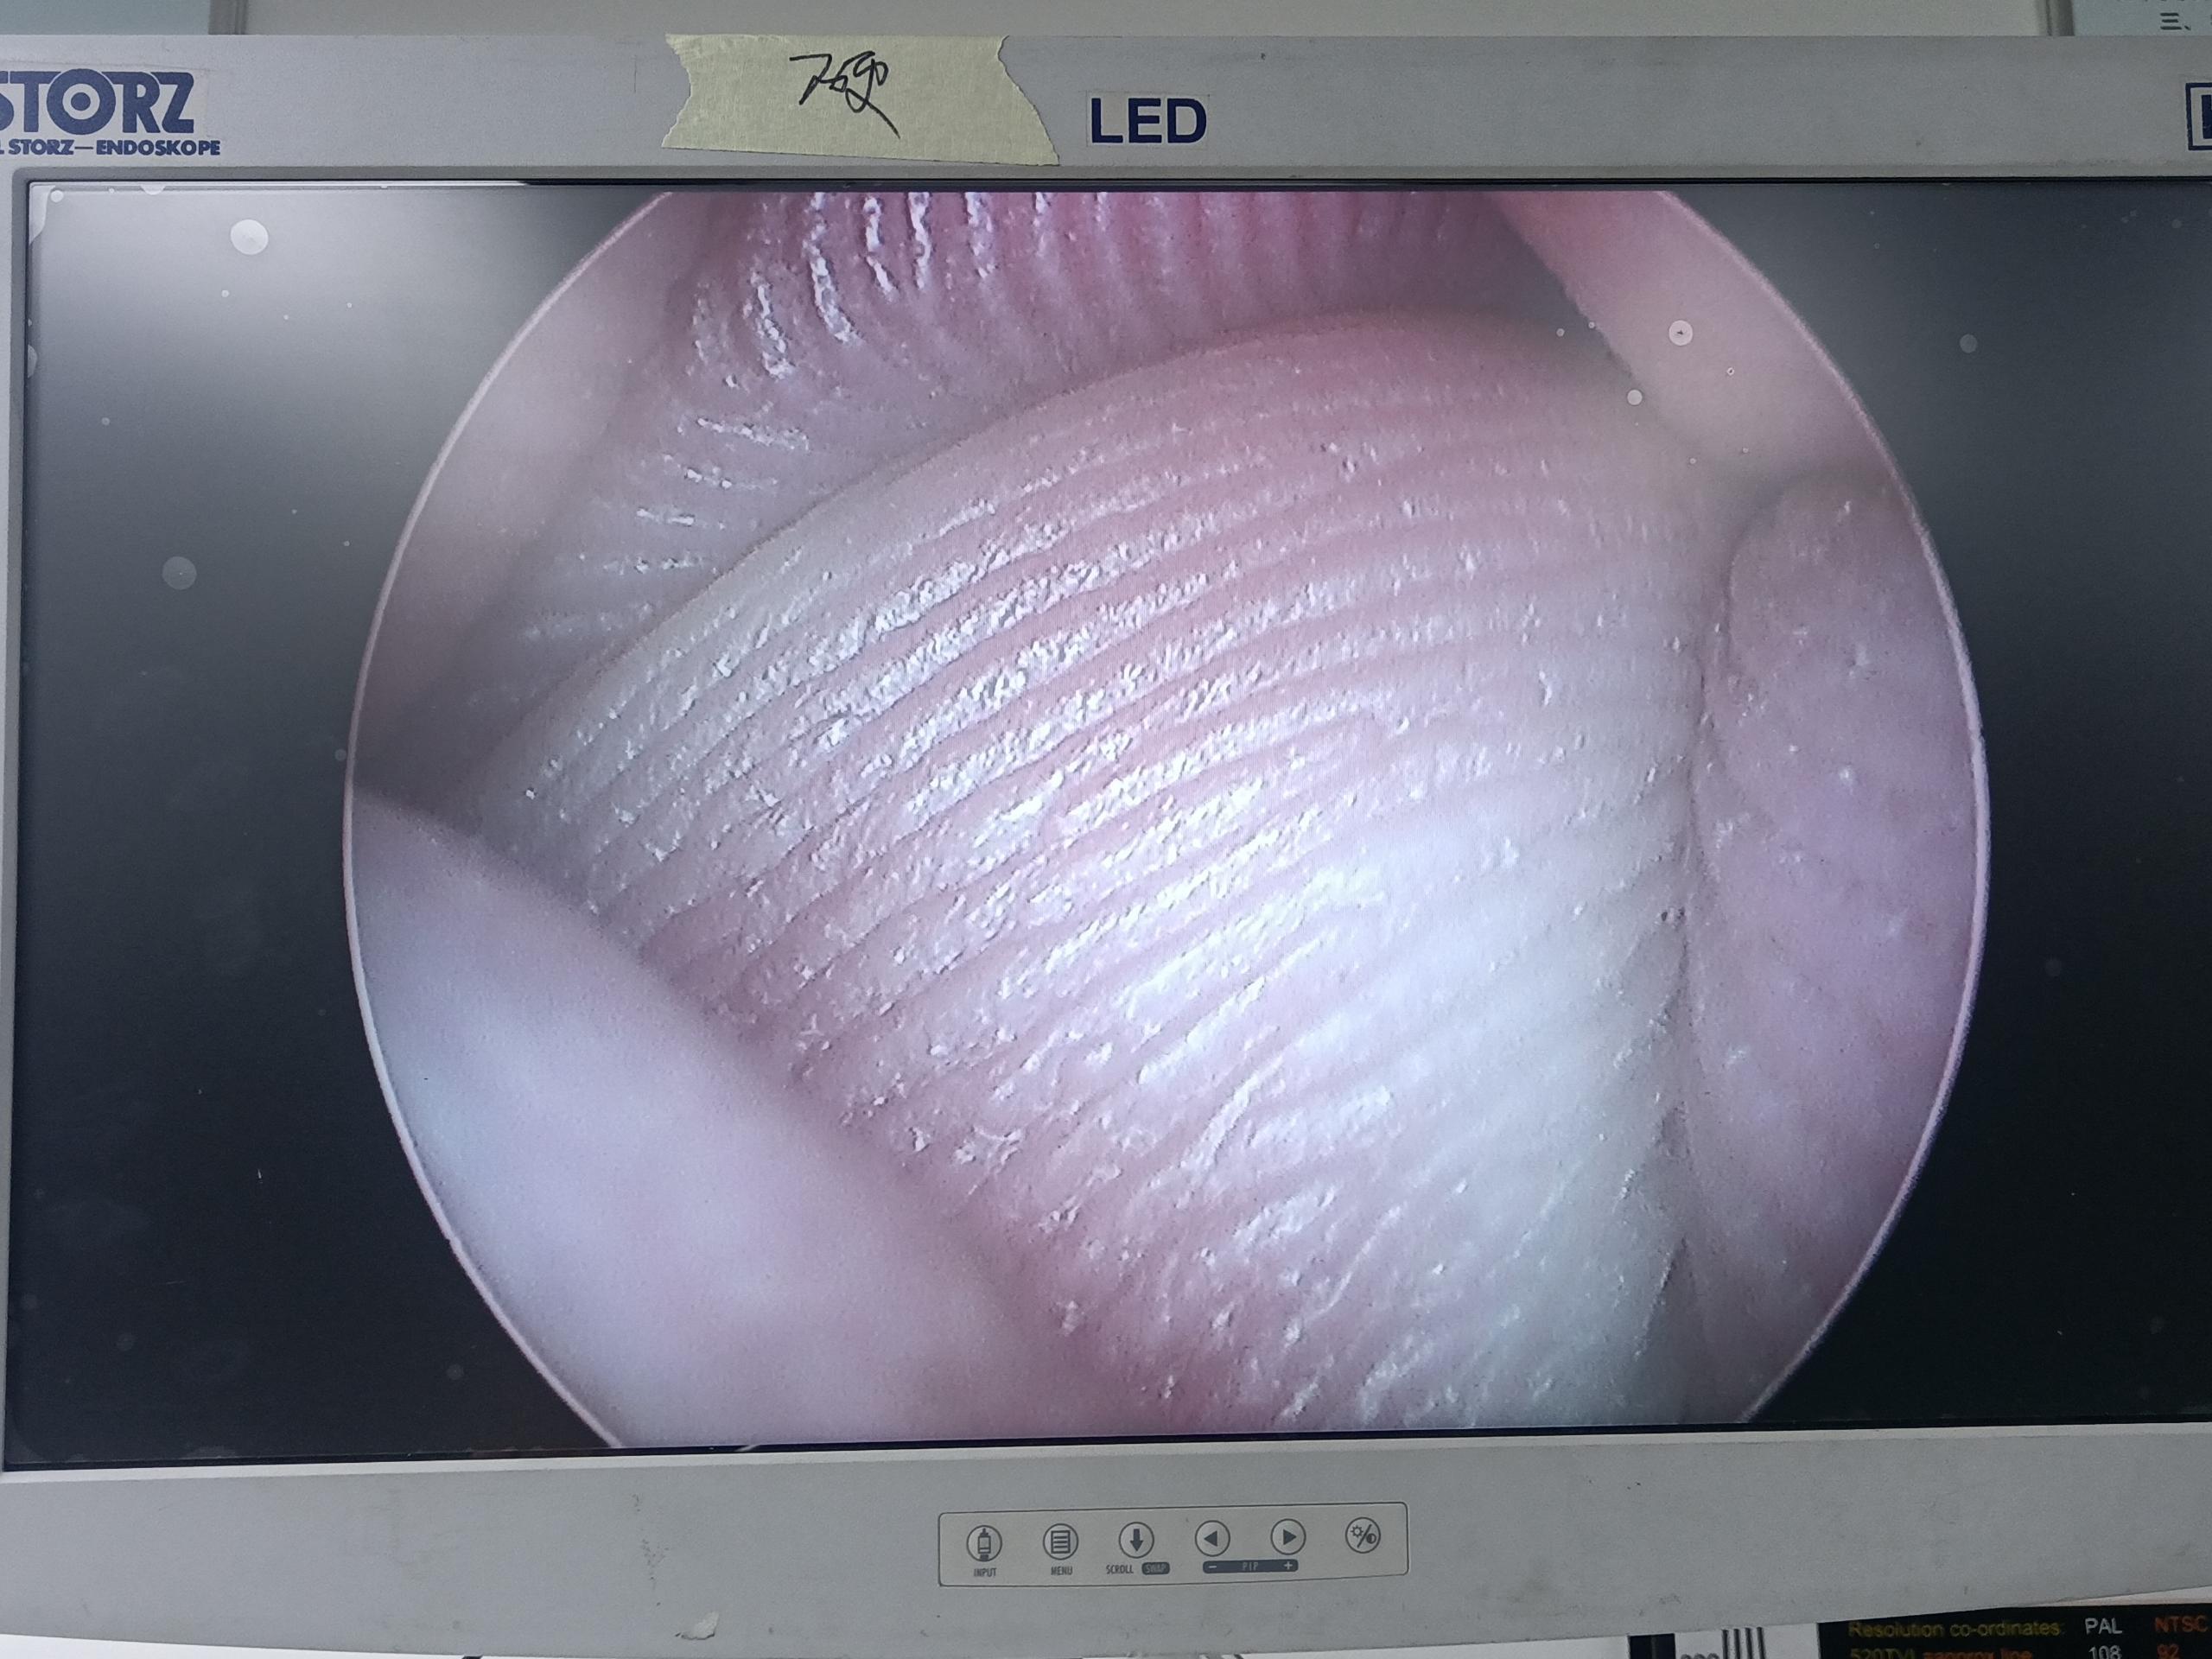

故障內(nèi)容圖像模糊,棒透鏡破碎,導(dǎo)光錐破碎,目鏡罩破碎,鏡身有磕碰,但不影響使用。

維修方案更換棒透鏡、導(dǎo)光錐、目鏡罩,校對圖像,內(nèi)窺鏡抗震蕩抗沖擊性能測試,內(nèi)窺鏡密封性性能檢測;內(nèi)窺鏡抗震蕩性能測試,內(nèi)窺鏡冷熱沖擊性能檢測。